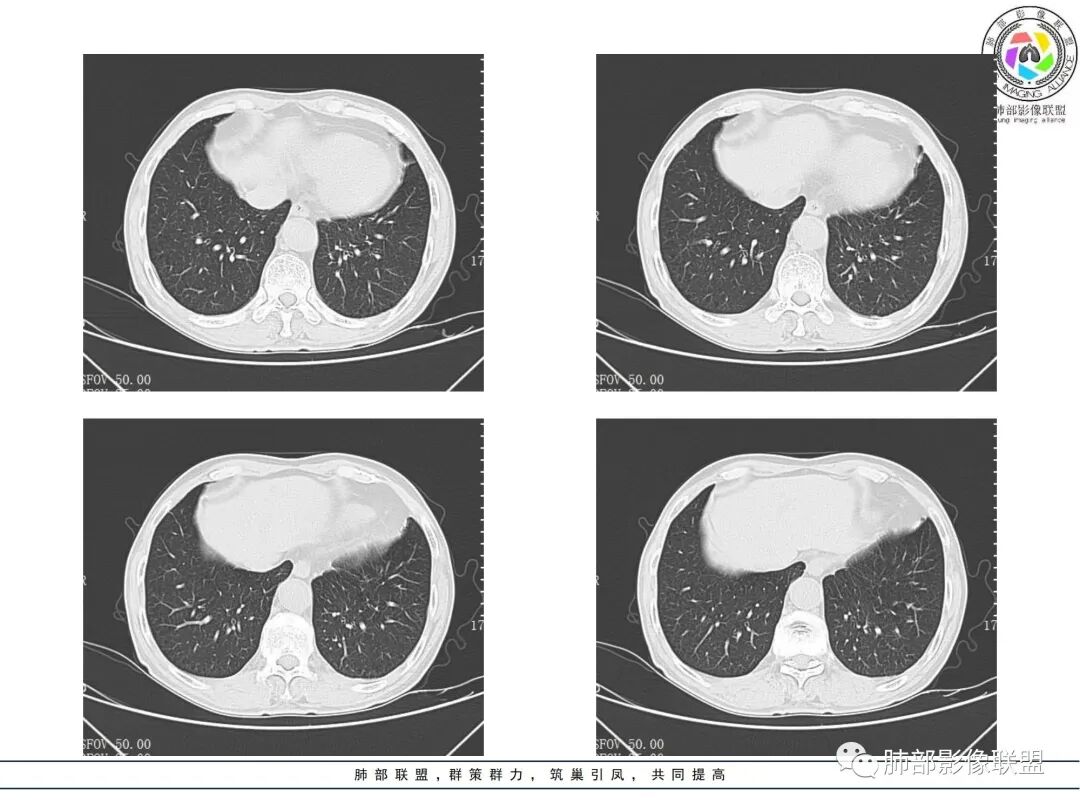

晨读病例,老年男性,乏力,纳差,近来发热,右肺上叶团片状阴影,内见空洞,空洞内壁不光滑,见短液平,增强病灶壁可见不均匀强化,似有边界不清晰的坏死,病灶周围可见片状模糊阴影,考虑恶性病变,鳞癌或腺癌伴感染。

老年男性,肺气肿背景,右肺较大分叶状肿块,密度不均,内坏死空洞形成,坏死区边界不规则,周围多发斑片蜂窝状、网格状高密度影,考虑鳞癌合并感染

右肺上叶及中叶不规则肿块伴周围模糊影,其内小叶间质结节样改变,肿块不均匀强化,坏死及空洞,坏死边界不清,血管显示尚可,考虑腺癌,鉴别淋巴瘤

老年男性,有咳嗽发热。右肺中上叶团状软组织肿块,周围磨玻璃渗出改变,病灶内密度不均,可见低密度坏死及空洞影,空洞内壁凹凸不平,近肺门侧可见明显大面积坏死。近端支气管堵塞不明显。考虑恶性肿瘤伴感染,腺癌?鉴别鳞癌,感染性病变。

右肺上叶团片状阴影,内见空洞,空洞内壁不光滑,偏心,,增强不均匀强化,内有边界不清晰的坏死,病灶周围可见片状模糊阴影,右下肺也有磨玻璃病灶,Crp高,腺癌

70岁男性,发烧病史,右肺巨大肿块,边缘分叶,内部空洞,洞内见附壁结节,局部支气管阻塞,肿块周围见大片阻塞性炎症;实验室检查,炎性指标增高;考虑恶性肿瘤伴阻塞性肺炎,鳞癌可能。

老年男性,乏力,纳差,发热。右肺上叶团片状阴影,密度不均,可见低密度坏死,坏死边界不清,可见空洞形成,见短液平;增强病灶呈不均匀强化,其内血管边缘模糊毛糙;病灶周围可见斑片状渗出病灶,支气管未见明确阻塞。综上考虑肺癌伴感染,鳞癌可能。

老年男性,纳差和发热,炎症指标明显。右肺磨玻璃影伴有肿块,肿块呈膨胀性生长,内部没有气管影。首先考虑感染,并有肿瘤的表现。考虑鳞癌合并感染

右肺上叶实变,密度不均,内可见小气液平,周磨玻璃影,斜裂稍内凹,右下肺可见斑片影,强化可见血管走行自如,右侧胸腔少量积液,考虑感染性病变,努卡?放线菌?

男,70,反复乏力、纳差20天,发热1天。胸部CT:肺气肿背景,右肺上叶中叶大团片影,实变十磨玻璃渗出。增强实性斑片影内密度不均,可见多发低密度坏死及不规则空洞影,空洞内壁尚光滑,血管边缘模糊。支气管管壁增厚,管腔通畅。右下叶可见小片渗出影。考虑支气管肺炎进展?病原考虑能形成肉芽肿、坏死空洞的微生物,TB?奴卡?鉴别鳞癌。

老年男性,乏力纳差,进食量明显下降,发热,后期少许黄脓痰,无咯血。无胸痛。未提口腔卫生情况,发热时间段不明确,肺气肿背景,气管内痰拴还是其他?觉得是外朝内进展病灶,右肺多叶段病灶,支气管通畅,支气管壁弥漫增厚,实变病灶内有坏死,坏死边界比较清晰,血管破坏不明显,周围散在磨玻璃,边界模糊,无树芽,实变内可疑小钙化,右侧胸水,肺门纵隔淋巴结无明显肿大。病史不太支持化脓菌感染,真菌里隐球强化不太支持,结核需要排除,厌氧菌感染带排,冠状位矢状位病灶觉得类圆形,临床肿瘤也是不能轻易排除的